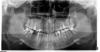

Dell Опубликовано 20 октября, 2010 Поделиться Опубликовано 20 октября, 2010 (изменено) Здравствуйте. После пломбировки зуба (25-й), появились проблемы - заложенность носа, слизь, по краю губы появилась раздражение (не знаю как точнее описать - на губе самый край кожи как будто отмирает). На снимке - в канале штифт, пломбировочный материал вышел за верхушку корня в пазуху, слизистая утолщена. Что скажите уважаемые доктора? Думаю нужно удалить пломбировочный материал из слизистой.Может стоит удалить этот зуб? http://www.imagepost.ru/thumbs/249/vxaV_full.jpg http://www.imagepost.ru/thumbs/249/NKEVisnbhK3Ewnhj4y_YaeKWpjfFFmZ.jpg http://www.imagepost.ru/thumbs/249/8qqhUx_u1HBsEfZGw.jpg http://www.imagepost.ru/thumbs/249/IMG_0450.jpg http://www.imagepost.ru/thumbs/249/IMG_04452.jpg Изменено 20 октября, 2010 пользователем Dell Ссылка на комментарий

Dell Опубликовано 23 октября, 2010 Автор Поделиться Опубликовано 23 октября, 2010 Полную чистку пазухи делать не нужно, просто убрать метериал и участок измененной слизистой. Соответственно травма будет минимальной. Доступ по типу резекции верхушки корня. Этот зуб двухкорневой, проблемный канал находится в глубине от кости, то есть резекцией можно было бы добраться, если бы корни поменять местами (это мнение опытного хирурга ЦЛХ). http://www.imagepost.ru/thumbs/253/0JfKNJTfVF_Oe4zJ0Ud6l2i1.jpg Ссылка на комментарий